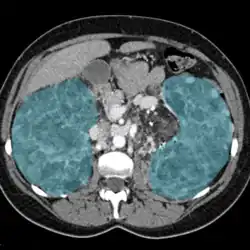

| Enlarged kidneys in blue | |